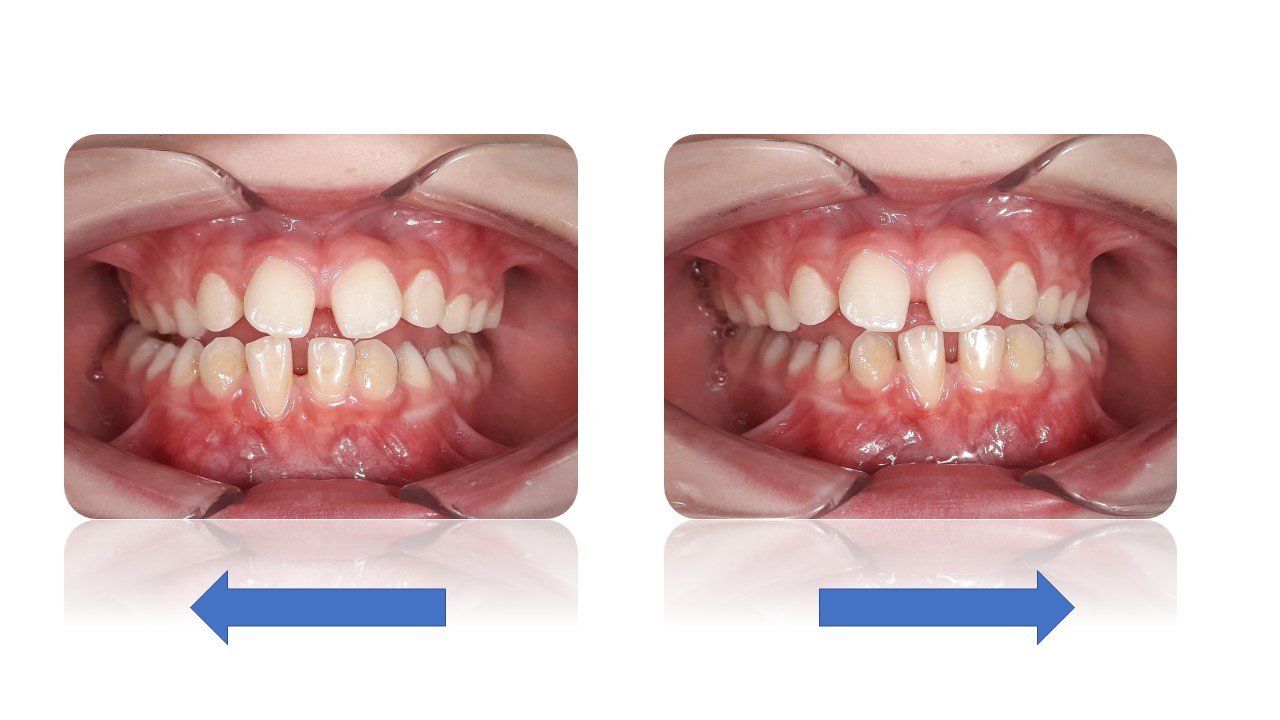

La Classe III Squelettiques

Les classes III squelettiques sont l’expression d’une orientation pathologique du plan occlusal et de la croissance faciale.

L’orthodontie systémique permet d’appréhender cette pathologie par l’analyse des latéralités mandibulaires.

Le traitement qui en découle est donc fonctionnel et stable car il permet non pas seulement une protraction du maxillaire mais une réorientation complète de celui-ci. Cette prise en charge permet de retrouver une proprioception maximale du prémaxillaire dans la mastication, gage de stabilité à long terme.